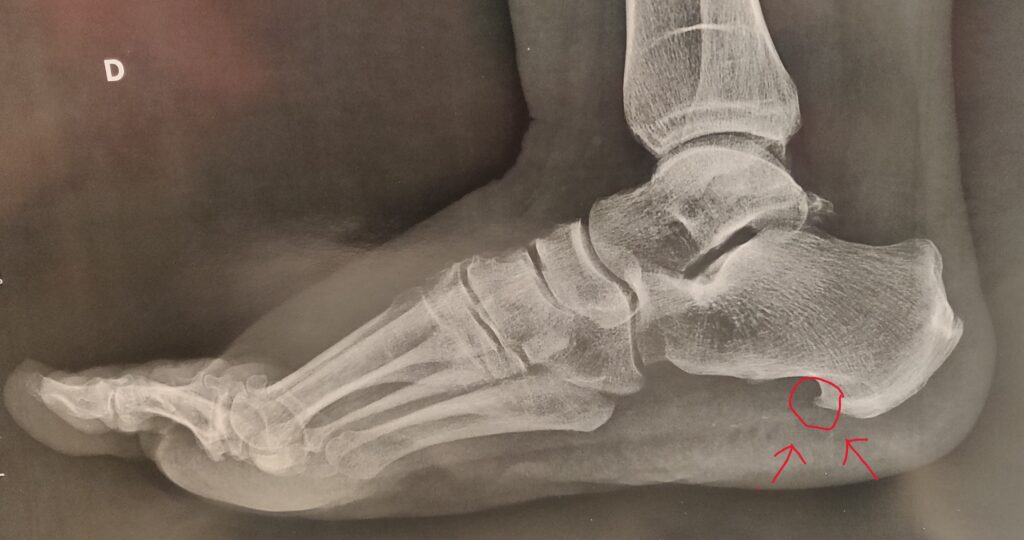

Radio

Une simple radiologie montre l’exostose en forme d’épine de rosier sur l’os du talon = calcanéum.